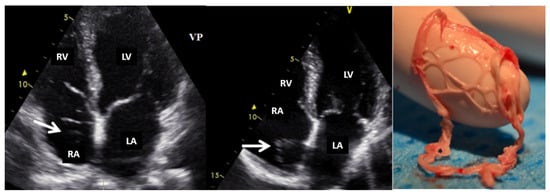

The diagnostic approach for right heart tumors is primarily based on differentiating them from other right heart masses such as thrombi (Figure 5) or vegetations (Figure 6). For example, in a patient with neoplasia and a port-a-cath (whether undergoing chemotherapy or not), a right heart mass discovered incidentally on TTE or TEE suggests a thrombus on the port-a-cath (Figure 5). It is less likely to be a benign tumor, especially considering the fact that these patients undergo repeated TTE evaluations. The initiation of anticoagulant treatment can lead to the resolution of this mass. However, a differential diagnosis is mandatory, involving considerations of marantic endocarditis or metastases.

Figure 5.

Two-dimensional transesophageal echocardiography (short-axis view at the level of the great vessels) showing a mass (arrow) on the port-a-cath in a patient with neoplasia and chemotherapy. It was an incidental finding. The mass disappeared after initiating anticoagulation treatment. AO, aorta; IVS, interventricular septum; LA, left atrium; LV, left ventricle; RV, right ventricle.

Figure 6.

Two-dimensional transesophageal echocardiography (short-axis view at the level of the great vessels) showing a mass (arrow) in the right atrium on the pacemaker leads. PM, pacemaker; RA, right atrium; RV, right ventricle; TV, tricuspid valve.

If the patient has a pacemaker or automatic implantable defibrillator, the first supposition in a clinical context suggestive of endocarditis is vegetation (Figure 6, Video S3—Supplementary Materials). A differential diagnosis must include fibrin formations or thrombi. However, if the patient is already anticoagulated (due to atrial fibrillation), these diagnoses are less likely.